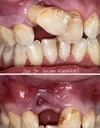

Diş Eksikliği

Diş ve Diş eti hastalıkları

Diş Çürükleri

Periimplantitis

Ağız diş ve çene cerrahisi